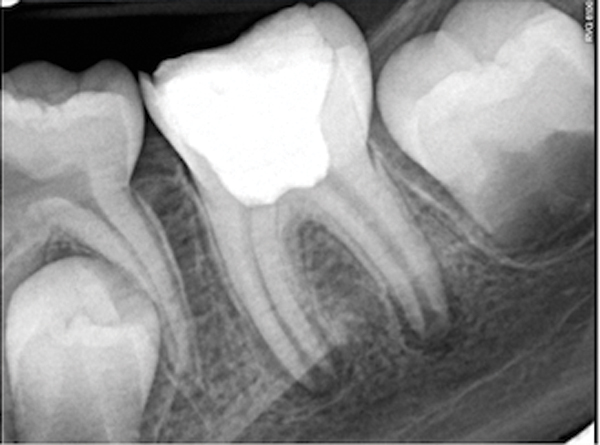

Fig 4. and Fig 5. Before and after radiographs of bioceramic sealer hydraulically moved with the gutta-percha point. Note that the cold hydraulic technique results in lateral canal “puffs” similar to the warm vertical technique. Courtesy of Dr. Gilberto Debelian.

Figure 4

Figure 5

Pre-mixed BC Sealer is the only pure medical-grade bioceramic product available as a sealer for endodontic obturation. It has the same basic chemical composition as the other pre-mixed bioceramic products, but it is less viscous, which makes its consistency ideal for sealing root canals. It is used with a gutta-percha point, which is impregnated on the surface with a nano particle layer of bioceramic. The gutta-percha is used primarily as the delivery device (plugger) (Figure 1 through Figure 3) to allow hydraulic movement of the sealer into the irregularities of the root canal and accessory canals (Figure 4 and Figure 5).